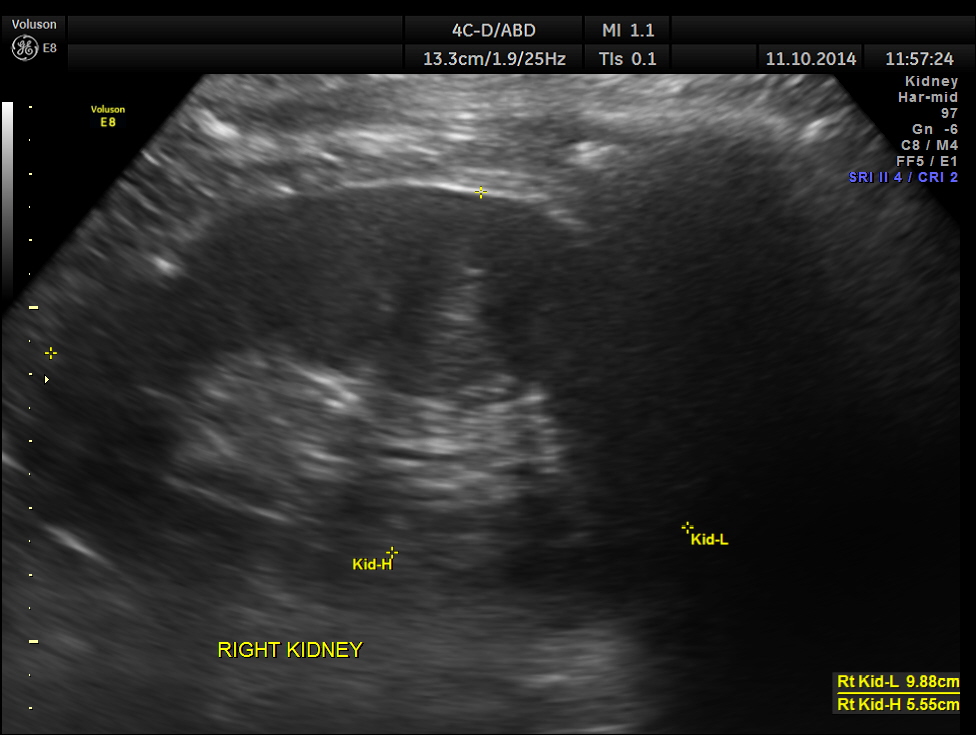

This was a 50 year old gentleman with history of occasional alcohol intake and complaints of tiredness and fatigue.

His ultrasound showed the following features.